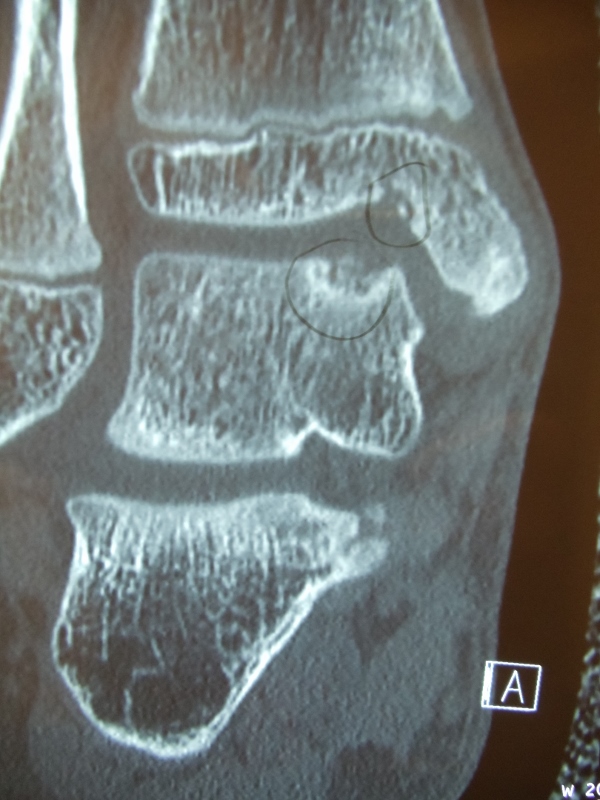

Series of Pics of Microfracture of large OCD of the Talar Dome

Pic of OCD after preparation and debridement .

Measuring the size and depth of the OCD.